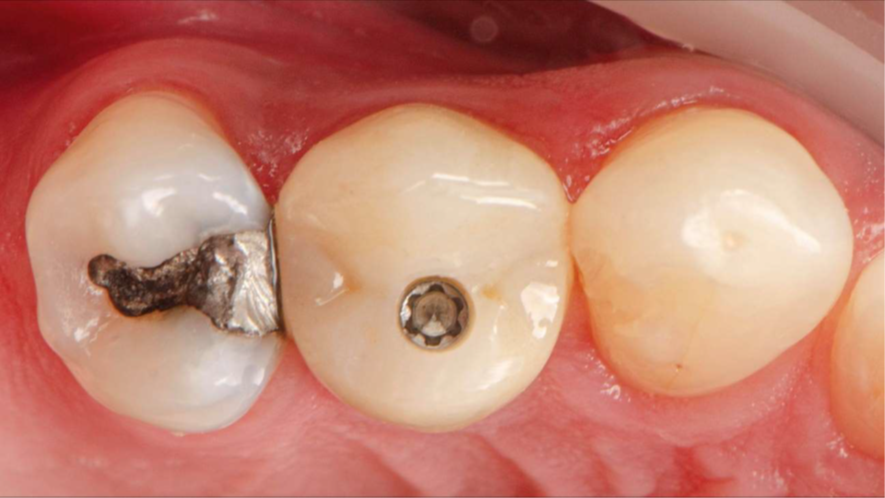

Após cerca de 120 dias em função, com perfil gengival consolidado, realizou-se escaneamento intraoral com transferente digital específico sobre o pilar Ideale. O fluxo digital eliminou moldagens analógicas, reduziu etapas e possibilitou desenho preciso do perfil restaurador.

A coroa definitiva foi fresada em zircônia monolítica maquiada, material estável, resistente e com baixa porosidade. Com resistência flexural entre 900–1200 MPa, permite restaurações finas com segurança mecânica e excelente longevidade clínica. A prótese foi parafusada diretamente sobre o pilar Ideale, utilizando o parafuso Torx com torque recomendado de 20 Ncm. O parafuso Torx apresenta tamanho menor em comparação ao parafuso convencional, o que otimiza o espaço interno disponível — especialmente relevante em regiões anteriores ou coroas com menor espessura oclusal. Sua geometria permite maior eficiência na transmissão de torque com menor risco de espanar, além de melhor acoplamento chave/parafuso, conferindo segurança durante a instalação e remoção. A instalação direta sobre o Ideale reduz interfaces, microgaps e micromovimentos, favorecendo selamento marginal mais previsível e estabilidade dos tecidos ao longo do tempo.